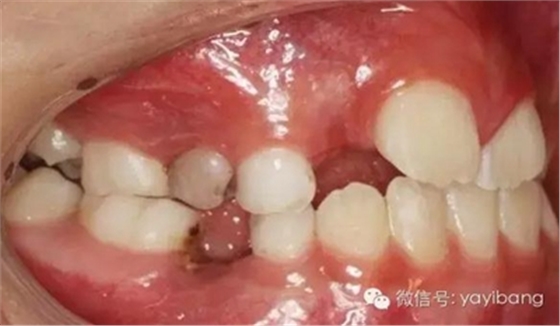

1、 患者 男 7歲 右下乳IV因齲早失

3、曲面斷層片 示恒牙萌出間隙不足